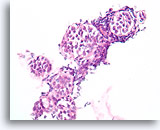

Papilloom, Borst FNA, Celblok.

Met een sterkere vergroting kan een gemengde celpopulatie gezien worden die het oppervlak en de onderliggende melkgangen bekleden. Een rij myoepitheliale cellen is zichtbaar tussen de ductale cellen en het onderliggende stroma (pijl). Let op de spleetachtige ruimte die kenmerkend is voor typische hyperplasie (open pijl).

40X

Papilloom, Borst FNA, Celblok.

Met een sterkere vergroting kan een gemengde celpopulatie gezien worden die het oppervlak en de onderliggende melkgangen bekleden. Een rij myoepitheliale cellen is zichtbaar tussen de ductale cellen en het onderliggende stroma (pijl). Let op de spleetachtige ruimte die kenmerkend is voor typische hyperplasie (open pijl).

40X